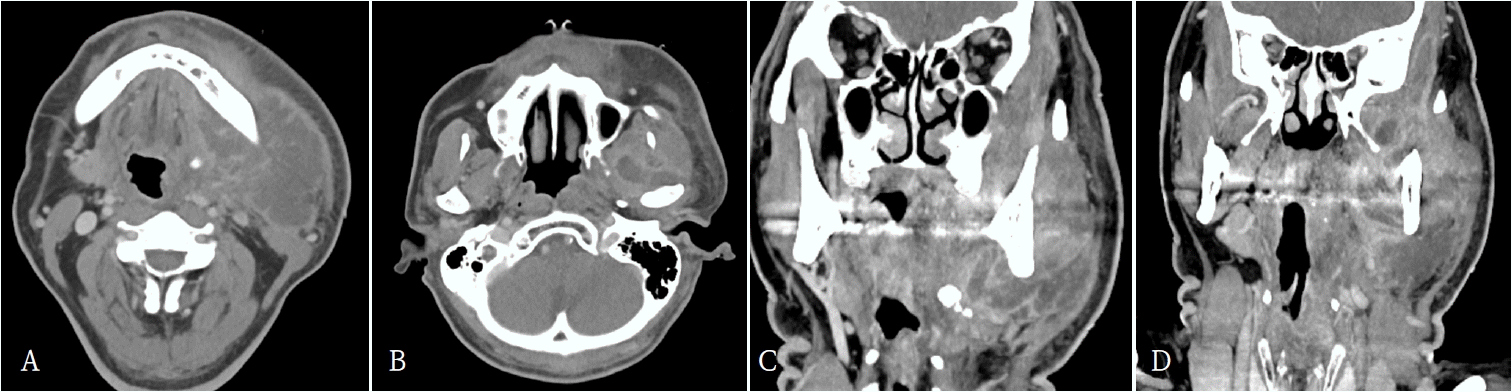

62세 남환이 3일 전부터 발생한 좌측 안면 종창과 입술 감각 저하를 주소로 본원 응급실에 내원하였다. 기저질환으로 당뇨병이 있었으며, 과거력에서 우측 하지에 발생한 괴사성 근막염으로 절개 및 배농술, 광배근 유리피판술을 수술받은 병력이 있었다. 내원 당시 좌측 하악각(mandibular angle)에서 악하(submandibular area)부위에 이르는 종창과 발적이 관찰되었다. 활력징후는 혈압 135/82 mmHg, 맥박수 122회/분, 호흡수 20회/분, 체온 37.8℃, 산소포화도 99%였다. 혈액검사에서는 백혈구 20.0 ×10³/μL, 호중구 84.5%(정상 40~75%), ESR 88 mm/hr(정상 0~10 mm/hr), CRP 270 mg/L(정상 0~5 mg/L)로 확인되었다. 조영증강 경부 전산화단층촬영(computed tomography; CT)에서는 좌측 악하부, 내·외측 익돌하악부(pterygomandibular space), 교근 및 인두주위(massteric and parapharyngeal space) 공간에 농양 소견이 관찰되었다(Fig. 1).국소마취 하 구강 내 및 구외 접근을 통한 절개 및 배농술을 시행하였으며, 항생제 정주 및 주기적 소독과 관류를 병행하였다. 초진 시 검사에서 HbA1c는 8.1%였으며, 식후 혈당은 200 mg/dL 이상으로 측정되었다. 이에 내분비내과와의 협진 하에 혈당 조절을 시행하였다. 치료 목표는 공복 혈당 80–120 mg/dL, 식후 혈당 <180 mg/dL로 설정하였으며, 이를 위해 Lantus 10 units, linagliptin 5 mg 1일 1회, metformin 500 mg 1일 1회를 투여하였다. 내원일부터 10일간 flomoxef 1g IV q12hr와 metronidazole 0.5g IV q8hr를 투여하였고, 배농된 농양에서 Klebsiella pneumoniae가 검출되었다. 그러나 입원 4일째 좌측 협부에 누공이 발생하였고, 이후 급속히 주변 연조직으로 감염이 파급되면서 광범위한 피부 및 근막의 괴사의 진행이 관찰되었다(Fig. 2).이에 수차례 국소마취 및 진정요법 하에 괴사 조직 제거와 음압 창상치료요법 드레싱을 시행하였으나, 상태 호전이 미미하여 입원 3주차에 전신마취 하 광범위한 절제술 및 농양 배농술을 추가로 시행하였다(Fig. 3). 이후 감염내과 협진 하에 적절한 항생제 치료와 면밀한 추적관찰을 지속하였고, 전신마취 수술 직후부터 항생제는 piperacillin/tazobactam 4g q6hr로 변경하였다. 입원 4주차에는 괴사 진행의 정체 및 혈액학적 지표의 호전을 확인하였다. 이에 하악 하 부위에는 부분층 피부이식(split-thickness skin graft)을, 좌측 협부 및 하악하, 관골 부위에는 유경 대흉근 피판술(pectoralis major flap)을 통한 재건을 시행하였다(Fig. 4). 수술 과정에서 좌측 심부 측두부와 안와 주위(periocular)에서 추가 괴사 조직이 확인되어, 이를 충분히 세척하고 괴사 조직을 제거하였다. 이후 1주일뒤, 환자에서 안와 주위의 지속적인 종창 소견이 관찰되었으며 영상검사에서 안와 주위 농양(pus collection)이 확인되었다(Fig. 5). 이에 안과 협진 하에 전신마취 하 수술을 시행하였다. 수술 접근은 눈꺼풀주름 절개(lid crease incision) 및 상안와 접근(supraorbital approach)을 통해 이루어졌으며, 수술 중 대량의 농이 배액되었다. 농 및 조직은 배양검사를 위해 채취되었고, 괴사된 안와 중격(orbital septum), 골막(periosteum), 누선(lacrimal gland)을 절제하였다. 재건 부위는 양호한 치유를 보였으며, 환자는 퇴원 후 외래 추적관찰 중 재발 소견 없이 회복되었다(Fig. 6). 이후 괴사성근막염의 치성원인으로 판단되는 좌측 하악 견치, 제1소구치, 제2소구치의 근관치료를 진행하였다.

Figure 1.

Contrast-enhanced neck computed tomographic images reveal abscess formation in the left submandibular space, pterygoid space (both medial and lateral), masseteric space, and parapharyngeal space. A and B. axial views, C and D. coronal views